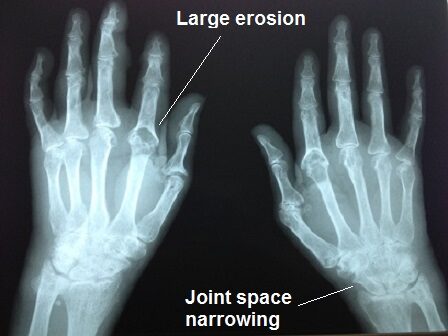

Rheumatoid arthritis: diagnosis